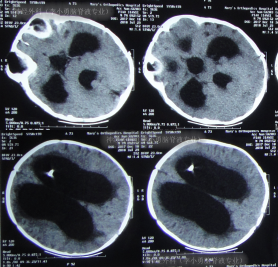

引流术后15天即2018年8月13日,眼球内聚“对眼”减轻,呕吐减少,查头颅CT示脑室缩小(图-5)。

图-5:2018年8月13日头颅CT

引流术后50天即28天即2018年9月17日,查头颅CT示脑室进一步缩小(图-7)。

图-7:2018年9月17日头颅CT